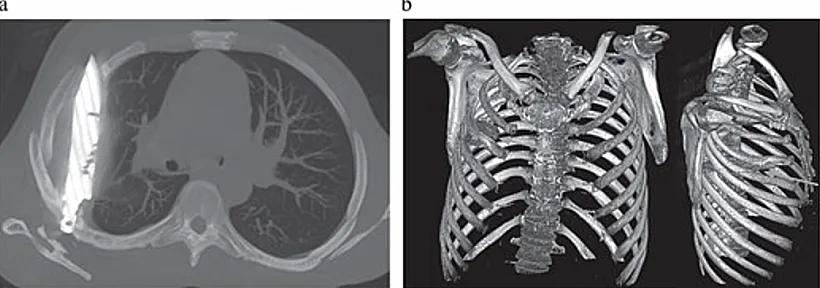

חי עם סכין בחזה במשך 8 שנים | צילום: Journal Of Surgical Case Report

הרופאים ערכו בדיקת רנטגן וגילו להב סכין שחדר דרך השכמה הימנית ונעצר בחלל החזה – מחמיץ בדרך נס את הלב, הריאות וכלי הדם המרכזים.

הצוות הרפואי ביצע ניתוח חירום להוצאת הלהב ולניקוז המוגלה שהצטברה ברקמות. לאחר הניתוח, המטופל שהה 24 שעות בטיפול נמרץ, ולאחר מכן הועבר למחלקה כללית למשך עשרה ימים.